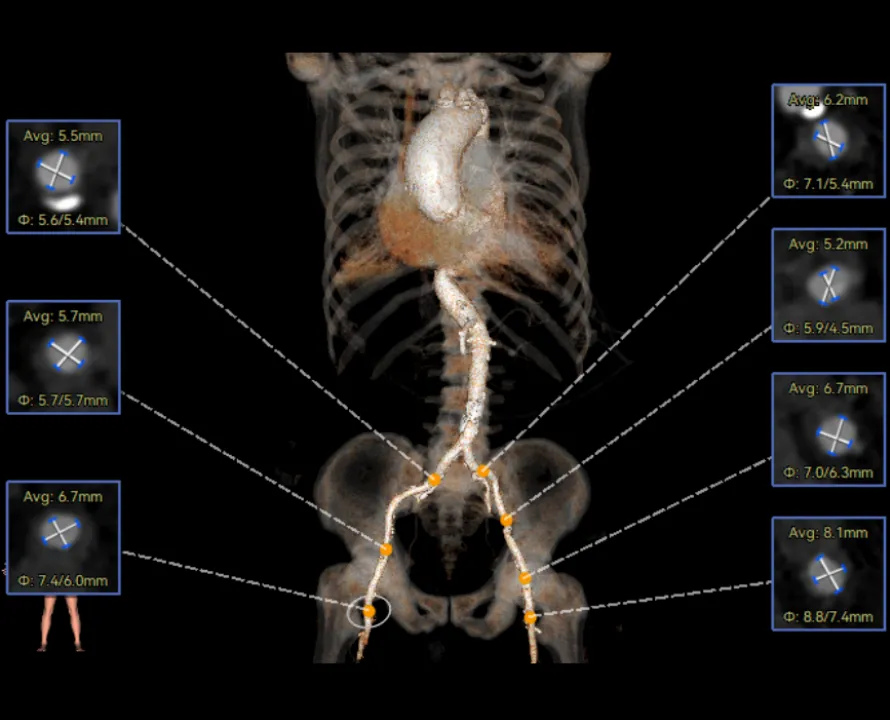

患者病史 主诉:发作性胸闷憋喘半年,加重伴呼吸困难2周。 现病史:患者半年前无明显诱因出现胸闷、憋喘,伴有下肢水肿,2周前上述症状明显加重,夜间不能平卧,痰中带血丝,为进一步诊治再次来我院,门诊以"心力衰竭"收入院。 既往史:肾功能不全、心房颤动 心脏超声提示:LVEF:0.54 1.主动脉瓣病变;2.主动脉瓣狭窄(重度)并反流(中度);3左室壁节段性运动不良;4.升主动脉扩张、双房扩大、左室肥厚;5.二尖瓣硬化并反流(中度);6.三尖瓣反流(轻-中度);7.肺动脉瓣反流;8.肺动脉高压(轻度)PGmean=105mmHg,Vmax=635cm/s,瓣口面积0.27cm²。 术前CT评估 Type0型二叶瓣,重度钙化,钙化集中在瓣叶游离缘,右冠窦为著;左冠高度11.8mm,由于左冠窦部空间较小,左冠风险较高, 升主动脉扩张,最宽处50.5mm;主动脉瓣环水平夹角61.5°,横位心。主动脉弓角77.6°,锐角弓,外周入路在腹主及髂总处有大量散状钙化,胸主处有81.6°的迂曲。 手术策略 推荐右侧股动脉为主入路,左侧股动脉为辅入路,送snare辅助过弯,使用18F大鞘,推荐预装ProStyle A® AV23瓣膜,20mm球囊预扩,初始定位对齐真实瓣环瓣上5mm超高位初始定位释放,释放过程中使瓣膜自然下滑,到工作位观察瓣膜形态,最终理想位置0-瓣下3mm。 手术过程 Step1:右侧股动脉为主入路、左侧股动脉为辅入路,成功穿刺并送入 18F 大鞘; Step2:主动脉根部造影,瓣口限制重 Step3:Type 0 型二叶瓣畸形合并重度钙化,患者瓣口狭窄严重,同时横位心,不仅导丝跨瓣困难,导管更难进入;术者凭借精湛操作,将导丝顺利跨瓣,反复微调导管角度,最终导管顺利过瓣。 导丝精准跨瓣 Step4:20mm球囊跨瓣困难,snare辅助下球囊成功跨瓣,预扩有腰无漏,冠脉充盈良好。 Step5: snare辅助下成功跨瓣,可以看到系统过弓形态瓣膜仓柔软,过弓顺滑 输送系统过弓 Step6:初始定位瓣上5mm开始释放,释放部分后观察瓣架下缘内收明显,后回收系统重新定位 初始定位 底部内收 Step7:瓣膜完全释放前,血压一度降低,术者迅速调整器械,实现瓣膜迅速锚定,快速释放 完全释放 Step8:20mm球囊后扩 最终造影,位置(瓣下3mm)形态良好 手术难点 患者不仅有主动脉瓣重度狭窄,还叠加肾功能不全、心房颤动等基础疾病,术中血流动力学波动极易引发心功能衰竭。ProStyle A® 预装干瓣“开包即用” 的特性压缩了术者操作时间,80%可回收设计给了术者容错空间,而这些看似难以逾越的难关,最终被团队精湛的医术一一化解,术中对于导丝、导管、球囊等器械每一步的精准操控,再到突发状况的从容处置,无不彰显着团队深厚的专业积淀与顶尖的操作技艺。 结语 此次手术的圆满成功,不仅彰显了陈玉国、李传保教授团队在复杂结构性心脏病介入治疗领域深厚的专业造诣与攻坚克难的决心,也充分验证了ProStyle A®系统在应对复杂高难度病例时的卓越适用性与有效性。 作为扎根齐鲁、享誉全国的医疗高地,山东大学齐鲁医院始终赓续着这片热土的仁厚文脉,将“医道从德,术业求精”的院训精神镌刻在每一次诊疗实践之中。特别是在结构性心脏病诊疗领域,医院团队始终怀揣医者担当,勇攀医学高峰,不断以更前沿的技术突破,为危重患者点亮重获新生的希望。 专家简介 陈玉国 山东大学齐鲁医院(点击查看专家详细简历) 李传保 山东大学齐鲁医院(点击查看专家详细简历) · END ·